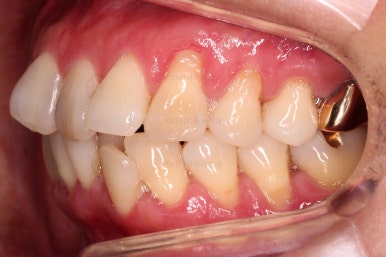

임플란트가 이미 있을 경우

임플란트는 교정이 되지 않습니다.

뼈에 단단히 붙어 있기 때문에 힘을 줘도 원하는 위치로 이동되지 않습니다.

이번 환자분의 경우 임플란트가 어금니 크기보다 작게 제작이 되어 있어서 추후에 교합을 맞추기도 곤란한 상황이었어요.

그래서 교정 후에 임플란트 뿌리 부분은 그대로 사용하고 머리 부분만 재제작 하기로 했습니다.